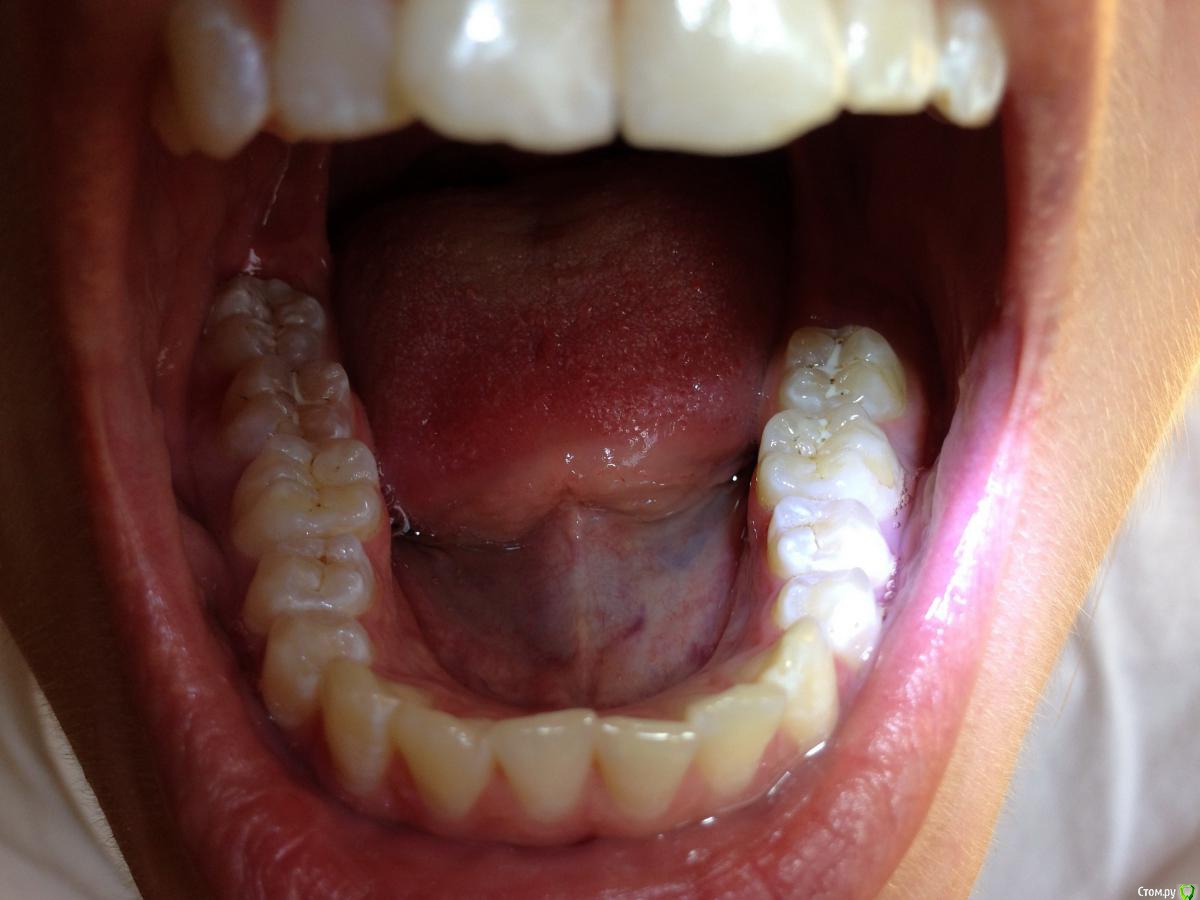

Ситуация следующая: сколько себя помню, всегда на зубах были белые пятна. Сейчас белые пятна почти на всех зубах и местами коричневые. Я не помню, когда появились коричневые пятна и очень беспокоюсь, что состояние эмали может в дальнейшем ухудшиться.

Врачи, у которых я консультировалась ставят разные диагнозы: флюороз, гипоплазия эмали. Рекомендуют наблюдаться и, к сожалению, не могут дать никаких прогнозов о развитии заболевания.

Фото зубов и снимок прилагаю. Буду очень благодарна за ваше профессиональное мнение.

Это у вас гипоплазия эмали вследствии флюороза, или так называемые крапчатые зубы. Что делать?, Ничего страшног просто участки с поврежденной эмалью очень хрупкие и поэтому выкрашиваются, просто пломбируйте, зато у вас устойчивостьт к кариесу повышенная